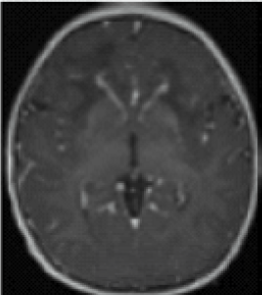

- Periventricular rim abnormalities (eg, high T1-weighted signal and low T2-weighted signal)1

- Contrast enhancement of 1 or more of the following structures: ventricular lining,

frontal white matter, optic chiasm, basal ganglia, thalamus, fornix, dentate nucleus,

and brainstem1